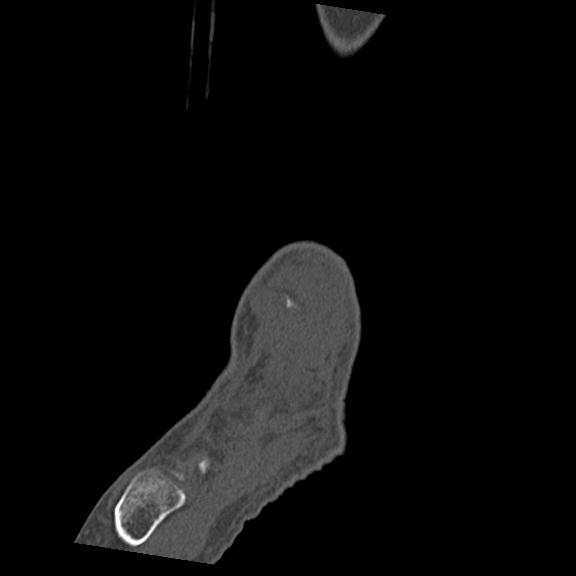

102755 1/4 2R 1/15 2R 右足関節 68歳女性 右三果脱臼骨折